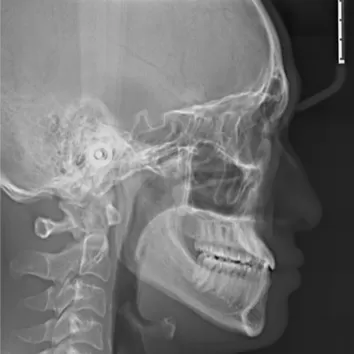

Rayons X avant le traitement

[Radiographie panoramique/Céphalogramme latéral]